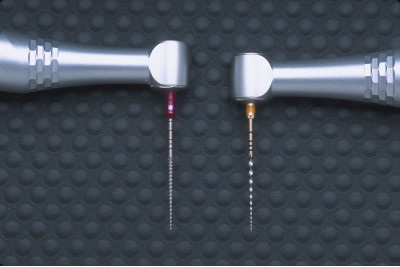

fișiere rotative New NiTi ProTaper face o adevărată revoluție în prepararea canalului radicular. 3 Acestea sunt special concepute pentru a oferi o bună flexibilitate, eficiență și mult mai mare de securitate. Caracteristici unice de proiectare permite clinicienilor de a ProTaper fișiere de peste si peste din nou pentru a crea formulare cu același conica în canale sau foarte dificile anatomic curbate (fig. 1 și 2). Kit-ul este format din numai șase (6) ușor de utilizat fișier, o serie de - a celor trei „formative“ și trei „finisare“ instrumentele care sunt în prezent disponibile în două dimensiuni: 21mm și 25mm (Figura 3). Următoarea secțiune descrie ProTaper geometrie.

Forming trei fișiere au diametre diferite D0. permitand clinicianului sa se deplaseze in conditii de siguranta mai adanc in canalul. În acest caz, fiecare lamă de pre instrument extinde zona în partea coronară a canalului. Noi Shaper №1 diametru D0 egal cu 0,17mm. Noi Shaper X - 0,19mm, în timp ce formatorul №2 - 0,20mm. Fișierele de finisare au diametre diferite D0. egală cu 0,20, 0,25 și 0,30mm, care corespunde în mod obișnuit la diferite diametre de îngustare apical. De obicei, necesită doar un singur fișier de finisare pentru a finaliza pregătirea în treimea apicală a canalului anatomic complex și curbat (Fig. 10).